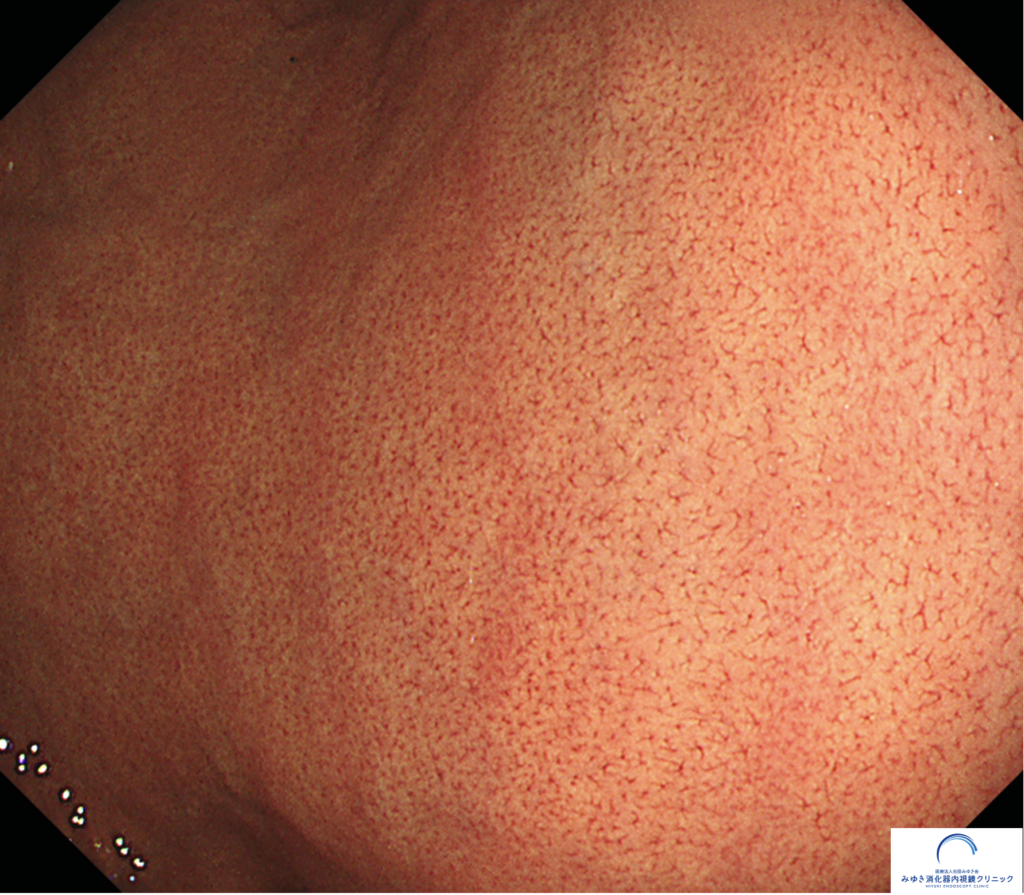

さらに、ピロリ菌に感染していない胃に発生することが多い胃底腺ポリープも確認されました。

その代表例が、胃底腺ポリープです。

「胃にポリープがある」と聞くと、不安に感じる方も多いと思います。しかし、胃底腺ポリープはがん化の危険性はほとんどない良性のポリープであり、過度に心配する必要はありません。

④ 胃底腺ポリープ

前述の胃底腺ポリープも正常な胃に見られます。RACが陽性で胃底腺ポリープが見つかった場合、その方の胃がんのリスクは低いと判断できます。そのため、胃底腺ポリープを「ハッピー(幸せの)ポリープ」と呼ぶ先生もいます。ただしピロリ菌の除菌後にも発生することがあります。